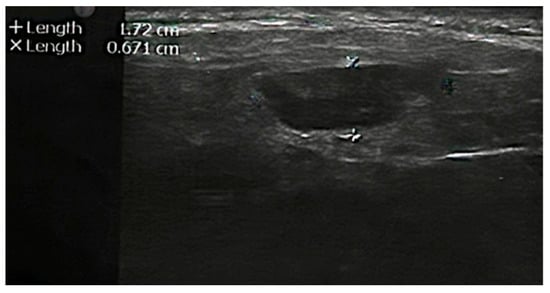

| 10 | Present case (2022) | 65 | F | 3.2 × 2 × 1.6 cm mass | 4 months, no recurrence |